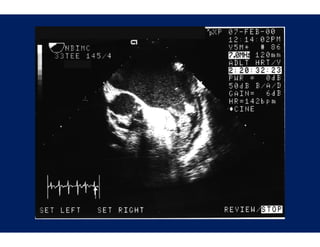

AF Tr

Haissaguerre, et. al.: N E

Engl J Med 1998;339:659-66

AF Tr riggers Haissaguerre, et al.: J Cardiova Electrophysiol 1996;7:1132-44 asc

AF Tr riggers Haissaguerre, et. al.: N E Engl J Med 1998;339:659-66

• 63.

Nathan, et. al.:Circulation 1966;34;412-22 u